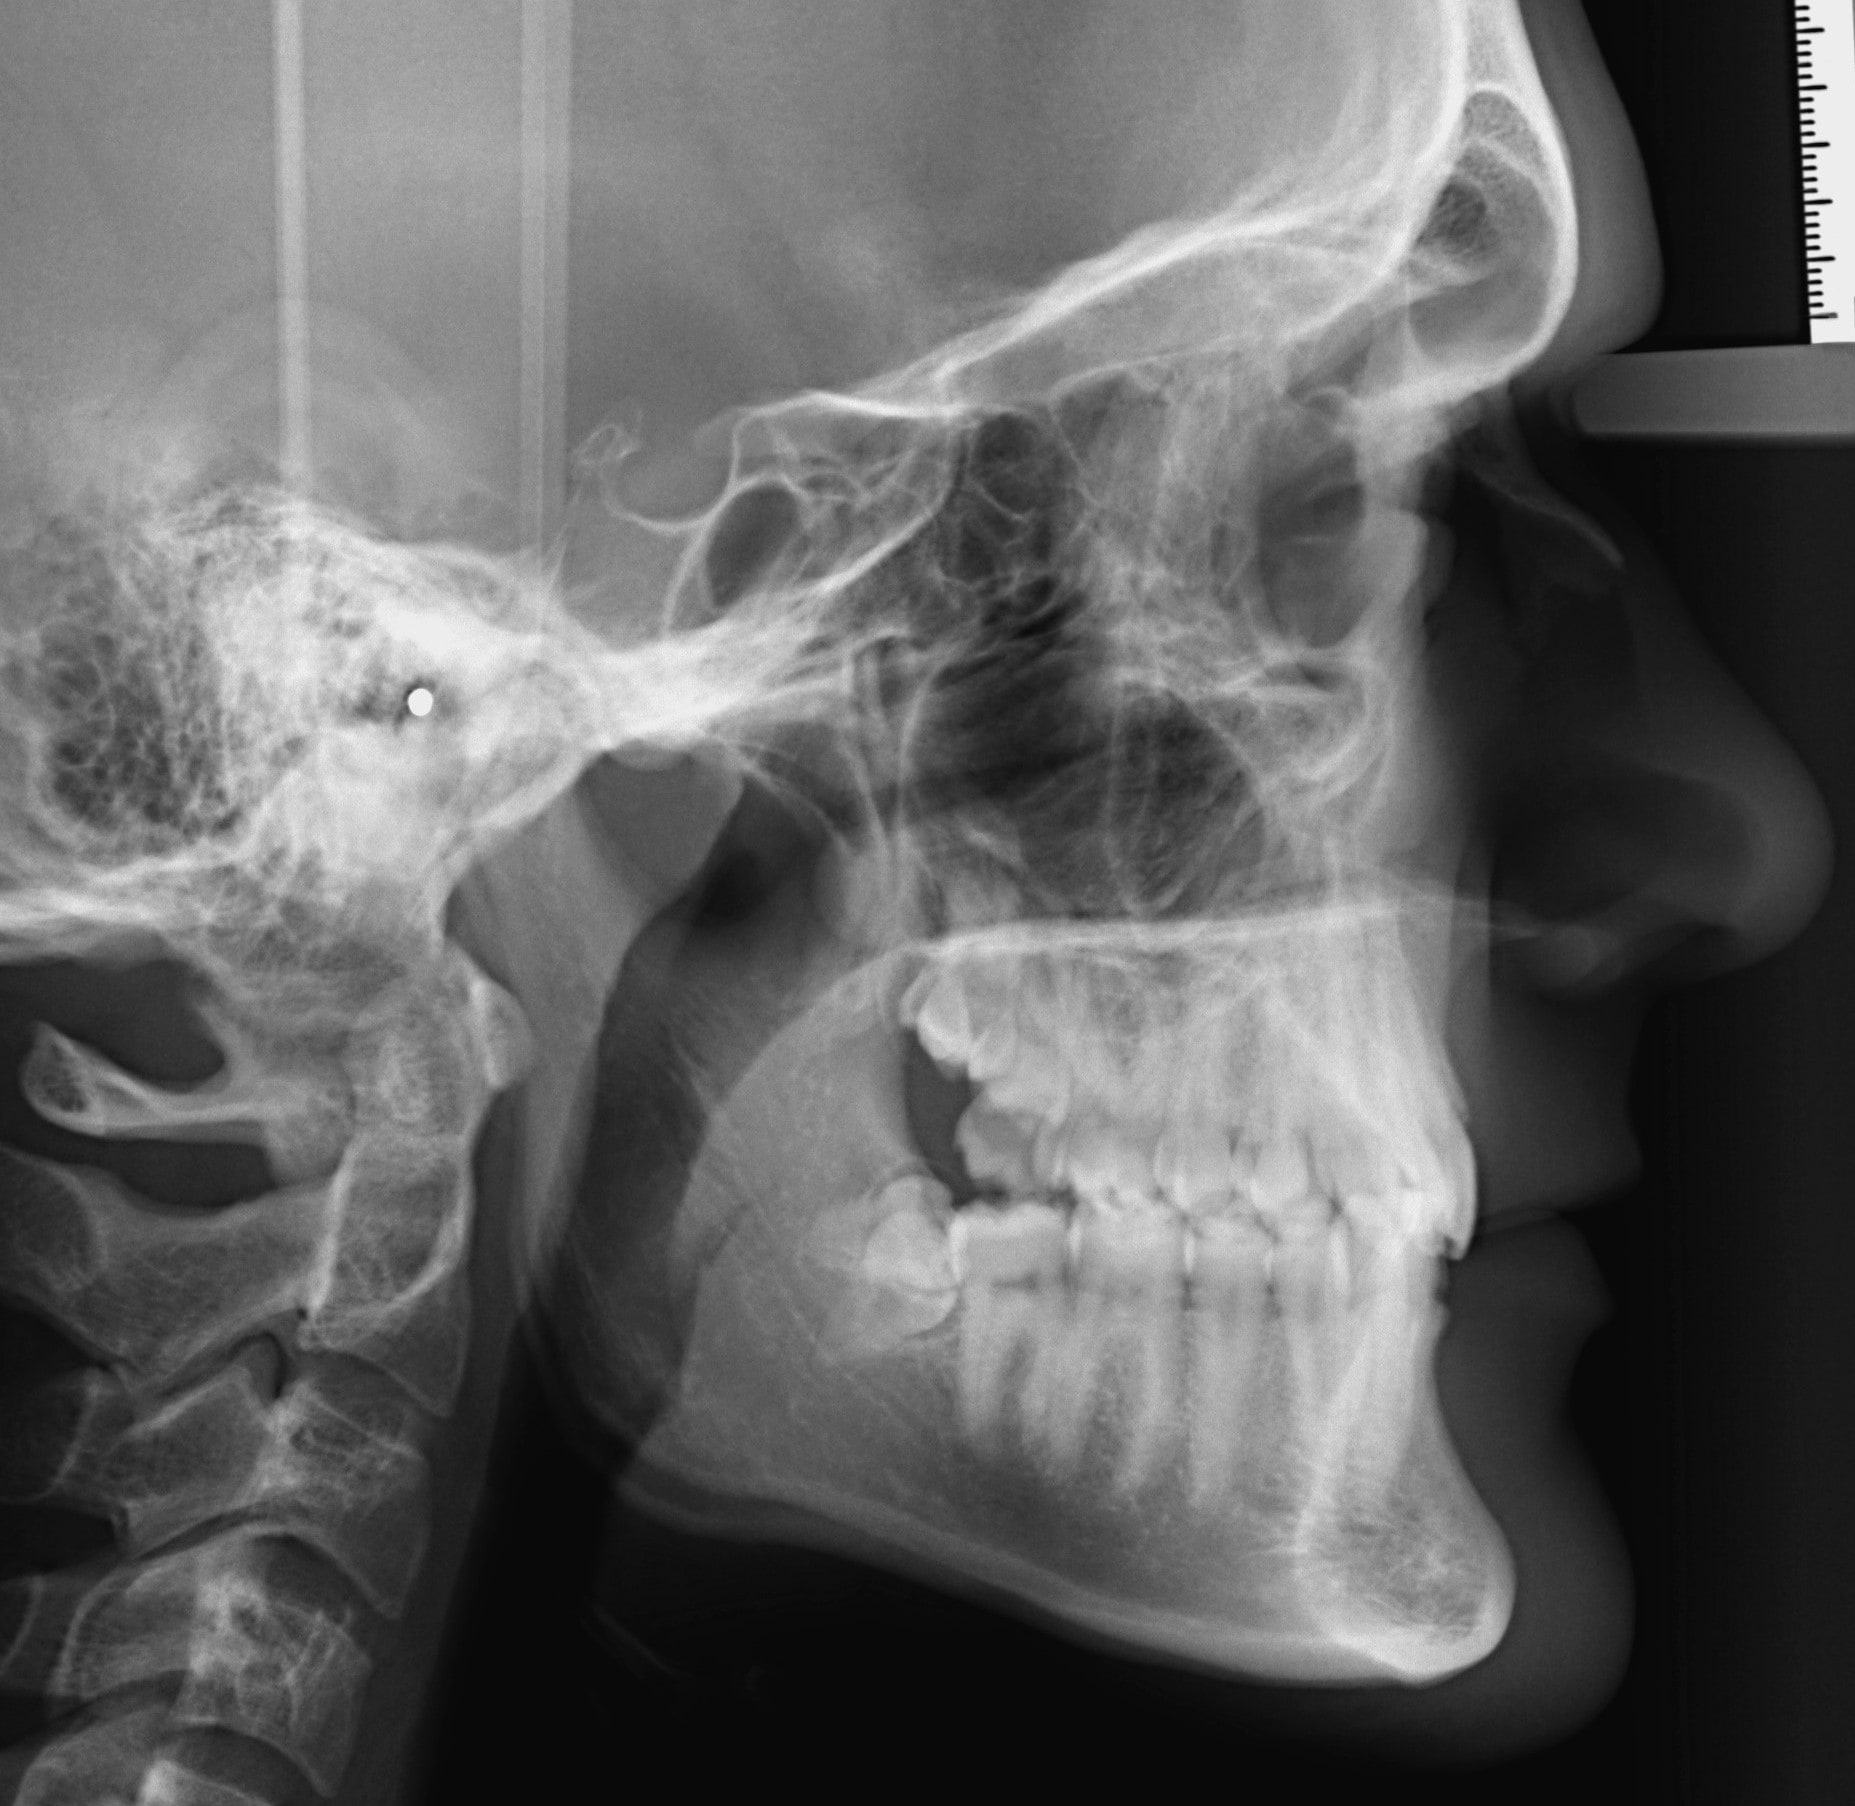

Nyakcsigolya érettségi besorolás (CVMS – Cervical Vertebral Maturation Staging)

Az oldalsó teleröntgenen látható nyakcsigolyák formájából, alakjából valamelyest következtetni lehet a gyermekek csontérettségi stádiumára. Számos készülék kizárólag adott stádiumban alkalmazható sikeresen. A besorolás 1-6-ig terjed. A kevésbé fejlett, differenciált nyaki csigolyákat a korábbi stádiumokba soroljuk (1-3. stádium), még az érettebbeket későbbiekbe (4-6. stádium). A CVMS is részét képezi annak a diagnosztikai összesítőnek, ami alapján eldöntöm, hogy melyik készüléket mikor alkalmazom. Például a bimaxilláris fogszabályozókat 3-4. stádiumban használom, a hyrax készülékeket a 2-3. stádiumban.

Oldalsó teleröntgen

Szinte 100%-ban fogszabályzási célból használt röntgenfelvétel. Gyakorlatilag egy oldalsó röntgenprofil. Látható rajta a metszőfogak tengelyállása, az állcsontok egymáshoz való viszonya a vertikális és szagittális síkban, elemezhetők a lágyrészek és a nyakcsigolyák. A nyakcsigolyák osztályozásával következtethetünk a páciens csontérettségi stádiumára is. A panoráma röntgennél is kisebb sugárterheléssel jár.